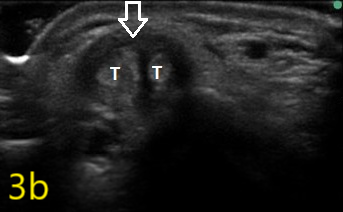

Image 3b

Ultrasound in Orthopedic Practice